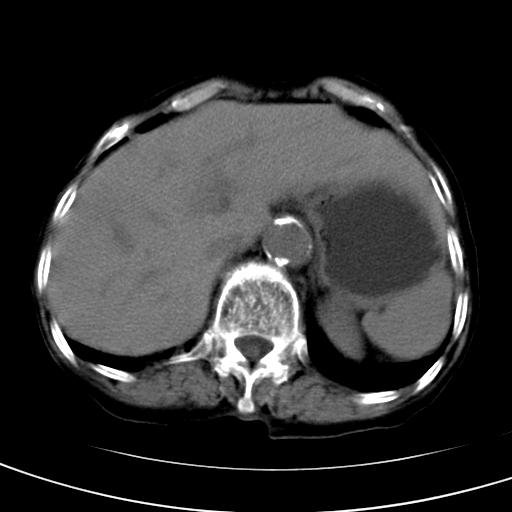

以下是引用wolft在2008-3-5 12:30:00的发言:[br]肝脏未见明显肿块影,但肝左叶增大,跨越腹中线到达脾胃前,且有一血管过去,考虑为先天变异:獭尾肝,胆囊为慢性胆囊炎急发,但胰腺头颈部有增大,密度不均匀,应该ct增强一下。

以下是引用zjzjr在2008-3-5 16:41:00的发言:[br]1.考虑慢性胰腺炎急性发作,建议增强除外占位性病变.[br]2.胆囊结石伴胆囊炎.[br]3.肝内胆管结石.